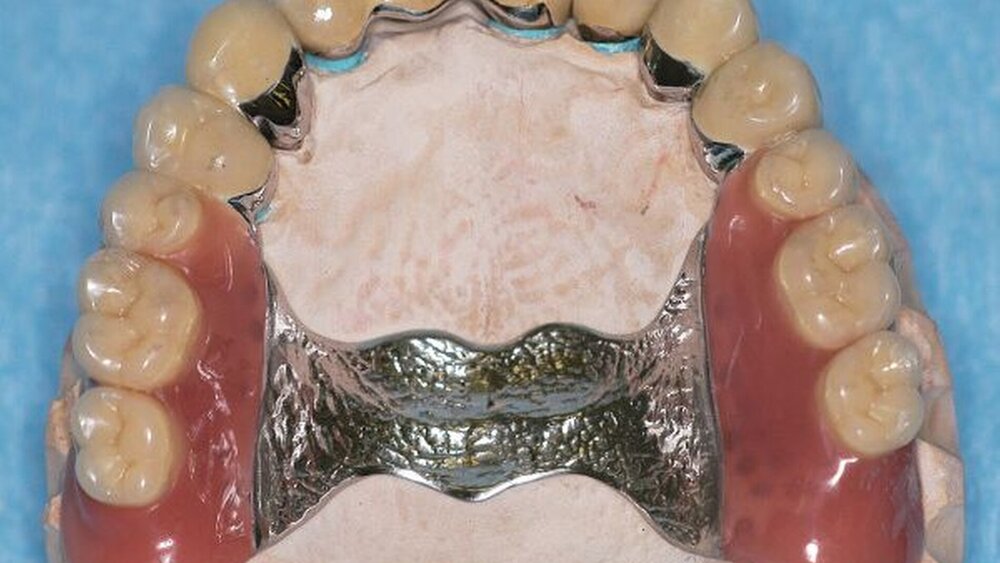

Mit dem Patienten wurden verschiedene Therapiealternativen diskutiert. Durch die werkstofftechnischen Rahmenbedingungen und die finanziellen Vorgaben entschlossen wir uns dazu, im Unterkiefer eine festsitzende Versorgung mittels zweier vollverblendeter VMK-Brücken von 37 bis 35 und von 43 bis 46 sowie vier vollverblendeter VMK-Einzelkronen (32 bis 42) anzustreben. Im Oberkiefer erfolgte die Planung im Sinne einer kombiniert festsitzend-herausnehmbaren Versorgung: vollverblendete VMK-Brücke 12 bis 21, vollverblendete VMK-Einzelkrone 22, Extraktion von 17 und 27, teleskopierend verankerte partielle Prothese mit den Pfeilerzähnen 14, 13, 23 und 24 (Abbildungen 6, 7, 8, 9, 10a, 10b, 11).

Nach durchgeführter Verblendung und Anfertigung des Sekundärgerüsts der partiellen oberen Prothese sowie Anfertigung einer separaten Wachsaufstellung wurden die Kronen und Brücken erneut anprobiert, um etwaige Änderungen die Farbe der Restaurationen betreffend vor dem Glasurbrand durchführen zu können. Zudem wurde die Sekundärkonstruktion der partiellen oberen Prothese auf ihre Passgenauigkeit hin überprüft. In einem letzten Schritt erfolgte dann die Beurteilung der Okklusion der Wachsaufstellung in Relation zu den angefertigten Kronen und Brücken.

In der darauf folgenden Sitzung wurden alle Kronen und Brücken sowie die teleskopgetragene, partielle obere Prothese für einen Zeitraum von sieben Tagen zum Probetragen mittels eines Zements auf Zinkoxid-Eugenol-Basis eingegliedert. Dem Patienten sollte durch das Probetragen der Restaurationen beziehungsweise des angefertigten Zahnersatzes die Möglichkeit gegeben werden, sowohl die Funktion beim Essen und Sprechen als auch die Ästhetik im sozialen Umfeld zu testen. Ein erneutes Entnehmen der Restaurationen wäre – für den Fall notwendiger Korrekturen – somit ohne Weiteres möglich gewesen. Da der Patient sowohl die Funktion als auch die Ästhetik betreffend keine Änderungswünsche vorbrachte und auch keine neuerlichen Beschwerden aufgetreten waren, konnten die Restaurationen nach besagtem Tragezeitraum von sieben Tagen entnommen, gesäubert und mittels eines Glasionomerzements definitiv befestigt werden. Im Anschluss wurden erneut Situationsabformungen der Kiefer genommen und der Patient erhielt nach erneutem Checkbiss-Registrat, eine okklusal adjustierte Stabilisierungsschiene im Unterkiefer. Diese dient der Therapie der beschriebenen Bruxismusproblematik und gewährleistet einen langfristen Erfolg der eingegliederten prothetischen Restaurationen (Abbildungen 13a, 13b, 13c, 14, 15a, 15b, 15c).